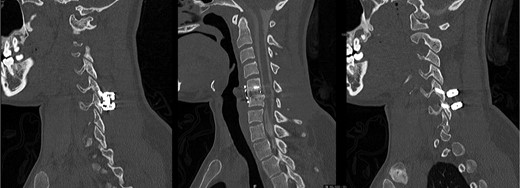

A computed tomography (CT) of the cervical spine without contrast revealed a C5-6 fracture dislocation and subluxation (Fig. 1) with spinal cord compression. The injury also included a posterior ligamentous complex rupture at C5-6, with fracture of the posterior lamina of C5 and right-sided jumped facet.

Preoperative CT, sagittal images through the center (left) and right side (right), illustrating the C5-6 fracture-subluxation and right jumped facet.